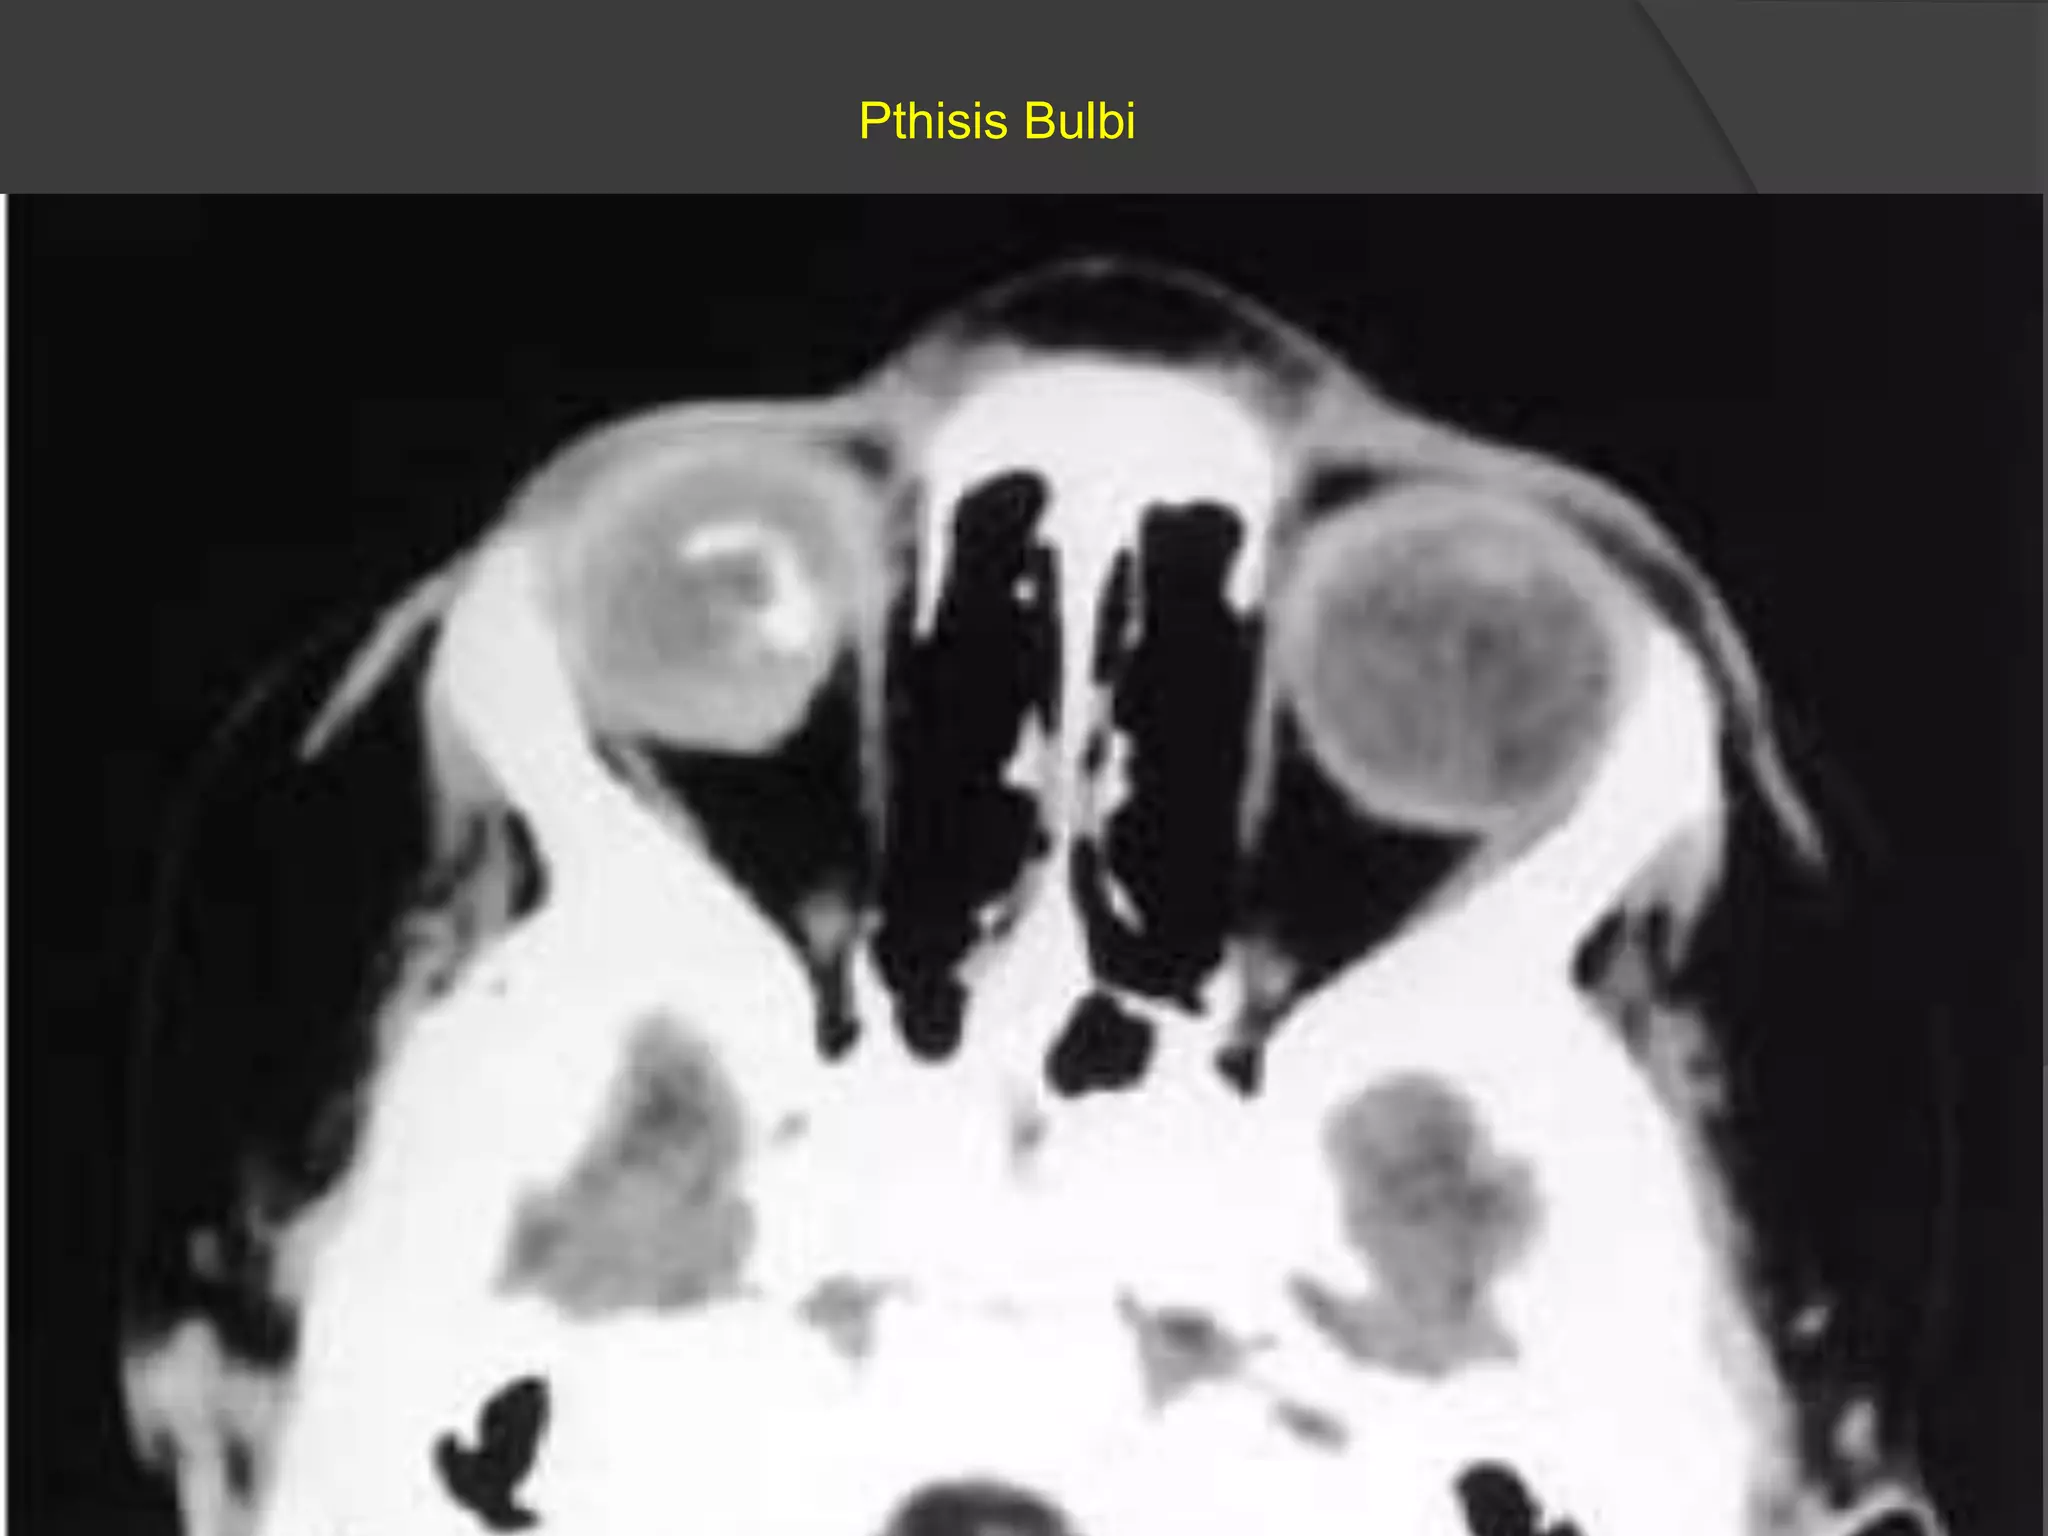

Pthisis Bulbi

• #6 Phthisis bulbi: Axial CT scan shows a dense right eye with irregular calcification. This child with acquired immune deficiency syndrome developed cytomegalovirus chorioretinitis, resulting in a disorganized eye with associated dystrophic calcification.